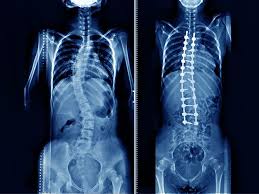

सर्वाइकल स्पोंडिलोसिस गर्दन (Cervical spine) के जोड़ों, हड्डियों (Vertebrae) और डिस्क (Discs) में उम्र के साथ होने वाली टूट-फूट (Degeneration) है। इसे आम भाषा में ‘गर्दन का गठिया’ या ‘आर्थराइटिस’ भी कह सकते हैं।

हमारी गर्दन की रीढ़ में 7 हड्डियां होती हैं। इन हड्डियों के बीच में गद्देदार डिस्क होती हैं जो शॉक एब्जॉर्बर का काम करती हैं। उम्र बढ़ने, गलत पॉश्चर, या चोट के कारण:

- डिस्क सूखने लगती हैं और पतली हो जाती हैं।

- हड्डियों के किनारे नुकीले होकर बढ़ने लगते हैं, जिन्हें बोन स्पर्स (Bone Spurs) या ओस्टियोफाइट्स (Osteophytes) कहा जाता है।

- गर्दन के लिगामेंट्स मोटे और सख्त हो जाते हैं।

जब यह टूट-फूट बहुत अधिक बढ़ जाती है, तो गर्दन के अंदर की जगह (Spinal canal) सिकुड़ने लगती है, जिससे वहां से गुजरने वाली रीढ़ की हड्डी (Spinal Cord) या नसों (Nerves) पर दबाव पड़ने लगता है।

- एक्स-रे (X-Rays): गर्दन का एक्स-रे यह दिखा सकता है कि क्या हड्डियों के बीच की जगह कम हो गई है या बोन स्पर्स (हड्डी का बढ़ना) बन गए हैं।